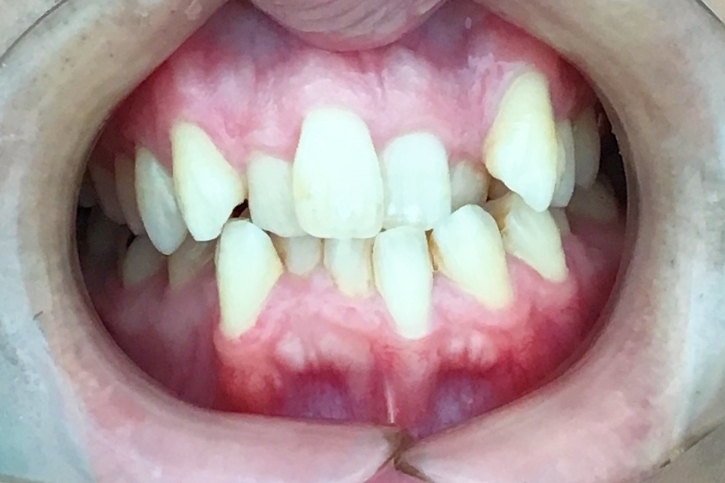

Before

浜松市中央区・自動車学校前駅のインビザラインの症例

After

Y.S. 30代男性

全体的にガタガタしているのが気になるという主訴だったため、上下左右第一小臼歯を抜歯し、叢生を並べました。

治療の期間:R3. 9/1〜R5. 10/31

治療の価格:88万円